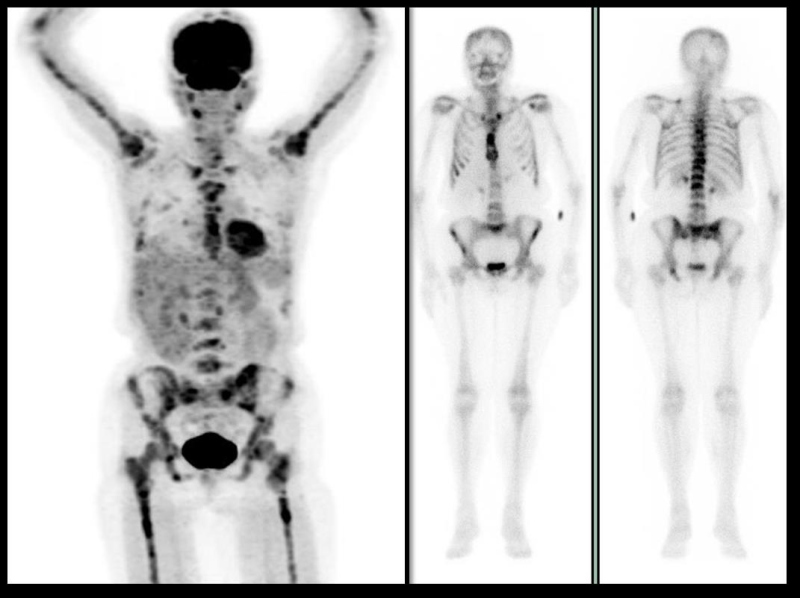

Figura 5.

Figura 5. Paciente de 73 años, con cáncer de mama metastásico de 4 años de evolución. Las diferencias en la captación de FDG (izquierda) y MDP (imágenes de la derecha) son notables. Las zonas de hipercaptación de MDP son menores en número y extensión que lo visualizado por PET-CT. El hipermetabolismo en el esqueleto apendicular, de patrón heterogéneo, corresponde a concentración en médula ósea compatible con infiltración neoplásica, cambios poco visualizados por la gammagrafía.